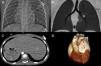

The authors describe the CT findings in a 29-month-old boy referred for cardiac CT angiography to assess complex congenital heart disease. The study was performed on a 128-slice prospectively ECG-gated dual-source Siemens Definition Flash system and showed mesocardia with abdominal/atrial situs inversus (Figure 1), atrioventricular and ventriculoarterial discordance with a subpulmonary ventricular septal defect, and a single coronary artery (Figure 2). Effective radiation dose was 1.0 mSv (dose-length product 25 mGy.cm).

Atrioventricular and ventriculoarterial discordance with a single coronary artery. Axial (A) and multiplanar (B, C and D) reconstructions showing atrioventricular and ventriculoarterial discordance, with anterior right aorta and posterior left pulmonary artery, infundibular septal defect with subarterial communication (asterisk), and anomalous origin of the right coronary artery in the left coronary sinus, coursing between the aorta and the pulmonary artery. AD: right atrium; AE: left atrium; Ao: aorta; CD: right coronary artery; Cx: circumflex artery; DA: anterior descending artery; P: pulmonary artery; VD: right ventricle; VE: left ventricle.

The patient was considered unsuitable for surgery due to the high surgical risk arising from the single coronary artery. This case illustrates the value of cardiac CT angiography for detailed non-invasive anatomical assessment of intra- and extracardiac structures, and was decisive in the therapeutic decision-making process.